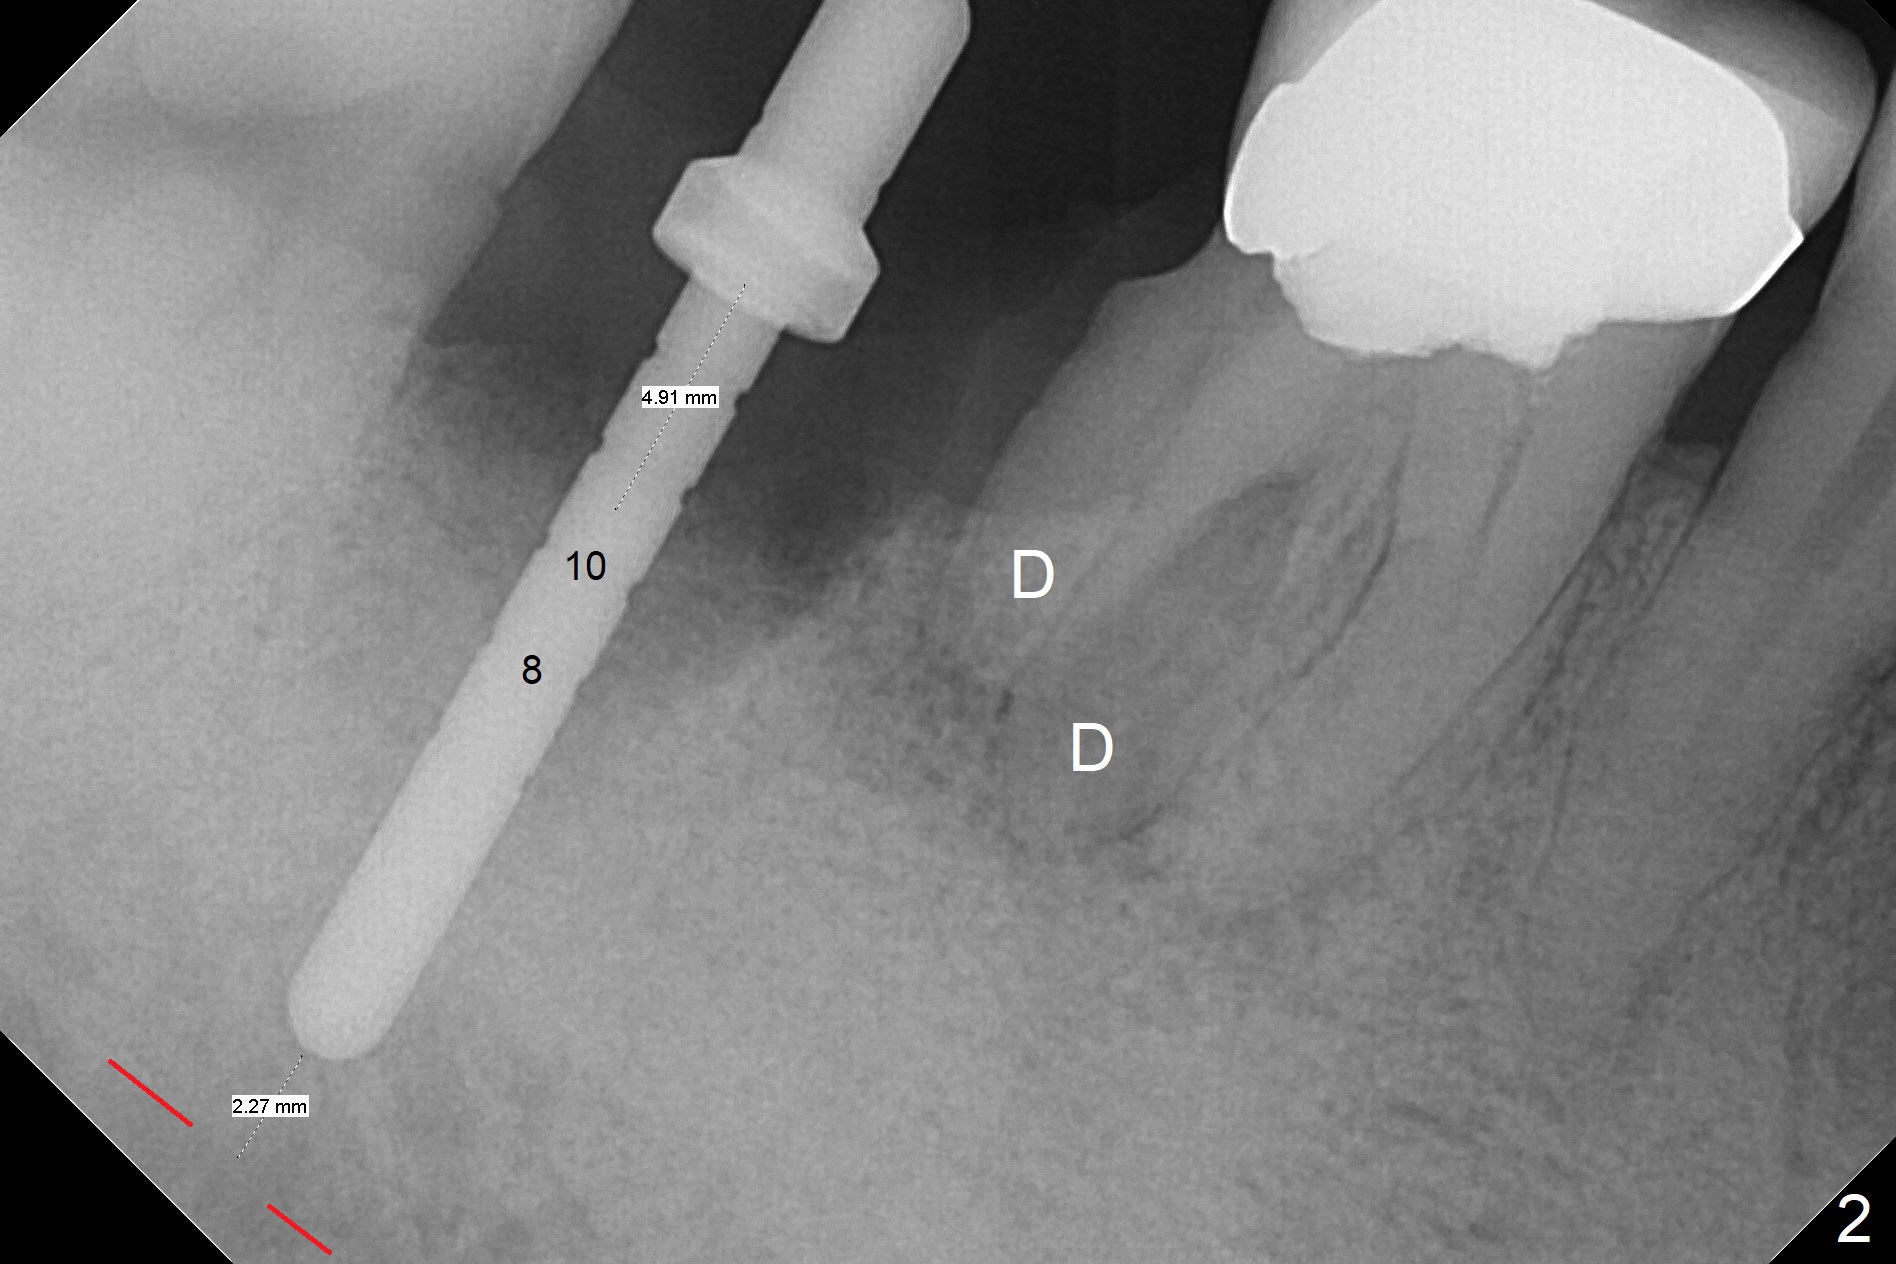

Although the tooth #30 has distobuccal root exposure (Fig.1 <), it is asymptomatic.  In contrast the tooth #31 with the distoocclusal caries (*) is symptomatic.  After use of 2 mm drill for 18 mm (lingual gingival margin), a calculated parallel pin is inserted (Fig.2 (D: 2 distal roots of the tooth #30)).  It appears that a 11.5 mm long implant is appropriate for the site; a 5 mm cuff is expected.  Following 4.8 mm drill, a 5.5x11.5 mm implant is placed initially (Fig.3) with an apical space (*) and clearance from the Inferior Alveolar Canal (red dashed line).  The implant is placed deeper with placement of a 6.5x4(5) mm abutment and bone graft (*, Fig.4,5).  After placement of collagen membrane over the graft, an immediate provisional is fabricated (Fig.6 P) with clearance from the opposing tooth (Fig.7 *).  There is no bone loss 3.5 months postop (Fig.8).  In fact the abutment has not been seated completely since its placement (Fig.4,5,8).  The crown/abutment dislodges 3 years 3 months post cementation (Fig.9).  The latter occurs for long incubation time because of opposing partial denture (Fig.10).  After trimming proximal surfaces (Fig.11: arrowheads), the abutment remains incompletely seated (Fig.11) due to possible crestal bone interference (Fig.11 *).  The smaller abutment by itself remains unseated (Fgi.12).  One size small one is completely seated (Fig.13).  Impression is taken.  Two weeks later the abutment margin is supragingival.  After screw torque at 20 Ncm, the crown is cemented with access hole.  Excess cement is removed.